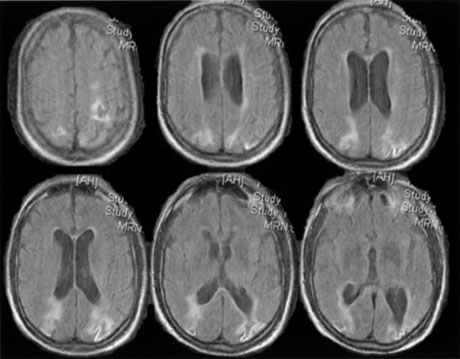

Bilateral lesions of striate cortex are not rare. Focal midline lesions such as tumors or traumatic injury may affect both striate cortices concurrently, because the right and left striate cortices face each other on the medial occipital surface. The most common cause, however, is posterior circulation ischemia.57 This can affect both striate cortices either simultaneously or sequentially,57 because the right and left posterior cerebral arteries have a common origin from the basilar artery. Twenty-two percent of patients with a unilateral occipital infarction develop bilateral infarction over 3 years.58 Bilateral incomplete hemianopia is distinguished from bilateral optic nerve or ocular disease by the high congruity of the visual fields and step defects along the vertical meridian which indicate the hemifield nature of the visual loss (Fig. 15).57 Such steps are important to seek with a skilled perimetrist, but even so they can be difficult to demonstrate with bilateral hemiscotomata from occipital pole lesions.59 Bilateral quadrantanopias can occur,47,48 often in patients with prosopagnosia and achromatopsia for example, and may mimic the altitudinal defects of optic neuropathy.

Fig. 15. Bilateral incomplete hemianopia. A 69-year-old man with decreased vision after prostate surgery. A. Fields show remaining central parafoveal vision with some sparing of inferior left quadrant. Note how the defect respects the vertical meridian. B. MRI shows bilateral medial occipital infarction, with sparing of the occipital poles, accounting for the macular-sparing bilaterally. (Courtesy of Dr. Lucia Vaina.)